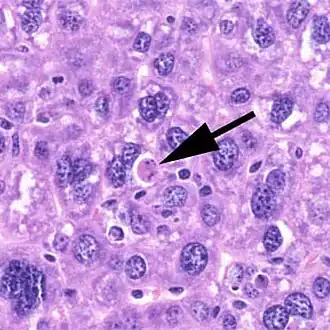

Histologie

Der Ablauf der Apoptose lässt sich lichtmikroskopisch verfolgen. Zuerst löst sich die betreffende Zelle aus dem Gewebsverband. Im weiteren Verlauf färbt sich die Zelle mehr und mehr eosinophil an und wird zunehmend kleiner. Außerdem bilden sich an der Zellmembran sichtbare Bläschen. Der Zellkern wird kleiner, sein Chromatin dichter gepackt. Er kann im Verlauf der Apoptose auch in mehrere Teile zerfallen. Am Ende des Vorgangs bleibt ein homogen eosinophiles Apoptosekörperchen. Dieses wird dann durch Phagozytose abgebaut. Der programmierte Zelltod löst dabei keine Entzündungsreaktion aus.[7]